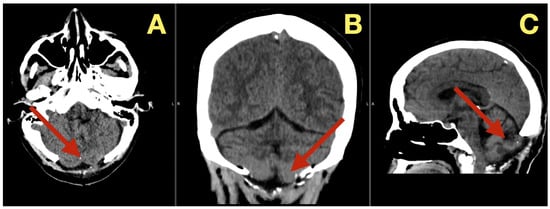

CT scans completed on the first post-operative day (Figure 3) were utilized to exclude hemorrhage and assess early ventricular diameter; they indicated posterior fossa re-expansion, full reopening of the fourth ventricle, normal brainstem convexity, and no early hydrocephalus. A second CT scan completed 7 days post-operatively (Figure 4) verified stable ventricular and outlet patency and excluded late onset hydrocephalus. The one month follow-up CT scan (Figure 5) provided a baseline for long-term comparisons. Later surveillance relied upon MRI including DWI to exclude diffusion-positive residual or recurrence.

Figure 3. Immediate postoperative CT scan. (A): Axial CT showing full decompression of the fourth ventricle and restoration of normal CSF circulation (arrow). (B): Coronal CT demonstrating complete midline re-expansion with absence of residual mass (arrow). (C): Sagittal CT confirming brainstem relaxation and normalization of posterior-fossa anatomy (arrow).